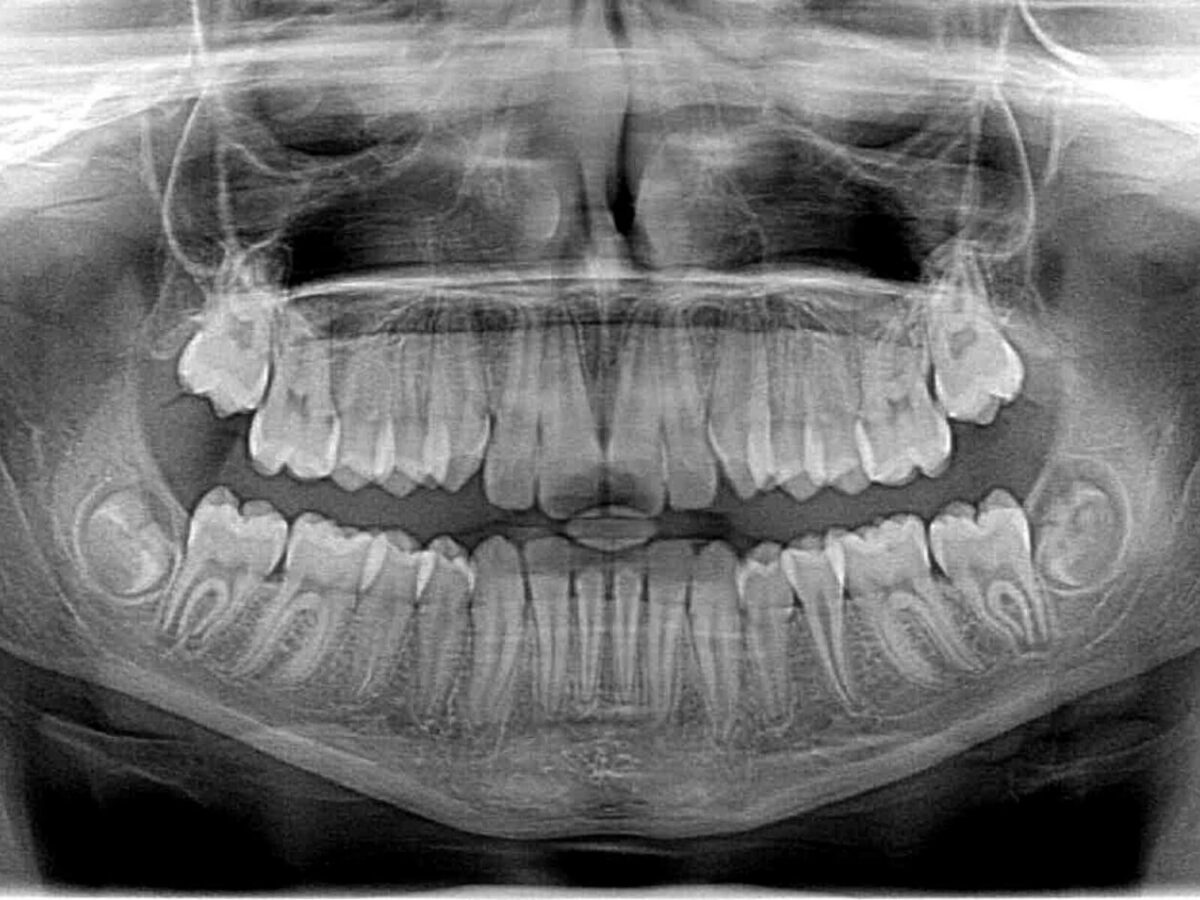

Digital X-rays do more than just show teeth. They help reveal what’s going on below the surface.

We’re talking about:

• Cavities hiding between teeth

• Infections at the root

• Bone loss

• Impacted wisdom teeth

• Early signs of gum disease

Things you can’t see with the naked eye.

Thanks to digital dental imaging, your dentist can zoom in, adjust contrast, and rotate angles. That makes it easier to catch problems early, when they’re small and easier (and cheaper) to fix.